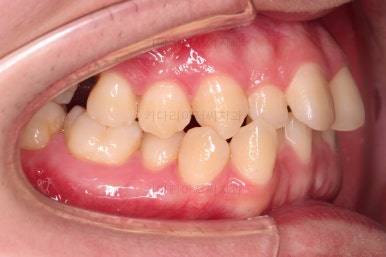

부산교정치과 초진 시 입안의 모습입니다.

앞니가 삐뚤어서 결손치아가 없었더라도 교정치료를 원하셨던 상황이었고요.

오른쪽 어금니 맞물림은 결손치아도 그렇지만 전반적인 앞뒤 차이가 있는 부정교합이 있었어요.